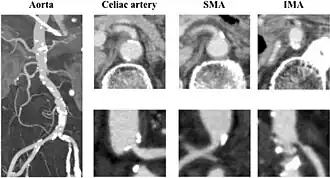

Enhanced computed tomography showing severe atherosclerosis of the arteries. The aorta shows broad calcifications, and the celiac artery shows moderate stenosis, although the lumen of the superior mesenteric artery was relatively patent. In addition, stenosis of the inferior mesenteric artery was very severe.

Abdominal angina is caused by obstruction or stenosis of the inferior mesenteric artery (IMA), celiac trunk, or superior mesenteric artery (SMA).[4] More than 95% of abdominal angina is caused by stenosis of the splanchnic arteries due to local atherosclerosis.[5][6] The occlusion mainly affects the ostia or the last few centimetres of the mesenteric arteries.[7]

In rare cases, compression of the celiac trunk by the diaphragm's arcuate ligament can result in isolated occlusive disease (also known as "median arcuate ligament syndrome").[5] Other less common causes of vascular obstruction include vasculitis, chronic mesenteric venous thrombosis, fibromuscular dysplasia, radiation enteritis, and, in rare cases, extrinsic obstruction or vessel encasement by a tumour.[8]